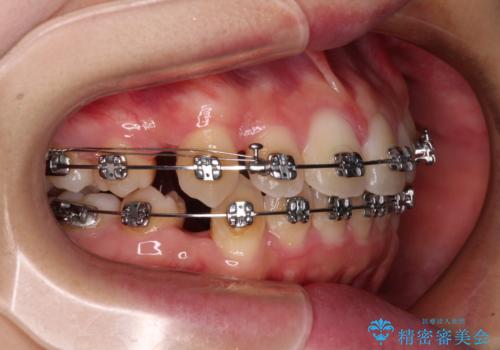

- メタルブラケット

- 1年9ヶ月

上下ともに歯列が前方に突出していたため、上下左右の第一小臼歯4本を抜去し、ワイヤー装置による矯正治療を行うこととしました。

上下左右4本抜歯する場合には、通常2年から2年半ほどの期間を要しますが、舌のトレーニングをしっかりと行っていただいたことで、1年9ヶ月で終了することができました。